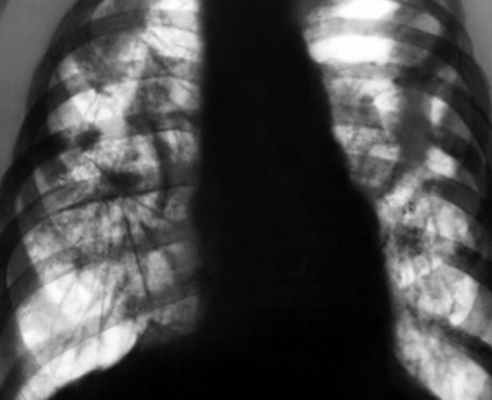

Рентген демонстрирует симметричные изменения, характерные для силикоза:

- На 1 стадии силикотуберкулеза в средних долях отмечается ячеистость, усиление легочного рисунка и его деформация, а также округлые мелкие затенения диаметром 2-3 мм.

- На 2 стадии сетчатость и ячеистость усиливаются и распространяются на другие доли – типичный легочный рисунок «исчезает», силикотические узелки обнаруживают по всем легочным полям.

- На 3 стадии обнаруживают массивные и интенсивные участки затенений, конгломераты.

Туберкулезные фокусы чаще визуализируются в верхних долях, они асимметричны, имеют различную величину и степень инфильтрации окружающих тканей. Контуры их нечеткие, интенсивность выражена не так ярко, как у силикотических конгломератов и бугорков. Силикотуберкулемы чаще имеют диаметр 2-4 см и внутренние включения; каверны при кониотуберкулезе приобретают неправильную форму.

На всех стадиях визуализируется краевое обызвествление внутригрудных лимфоузлов. Точный диагноз при сомнениях позволяет поставить компьютерная томография.

Рентгенологически при силикозе очаговые (узелковые) изменения определяются преимущественно в средних, частично в нижних и реже в верхних отделах легких на фоне значительного диффузного, грубосетчатого и тяжистого фиброза. Корни легких при этом расширены, уплотнены и часто как бы обрублены. Большое значение при дифференциальной диагностике силикоза, силикотуберкулеза и диссеминироваииого туберкулеза имеет, конечно, соответствующий профессиональный анамнез, а также различный эффект от туберкулостатической терапии.